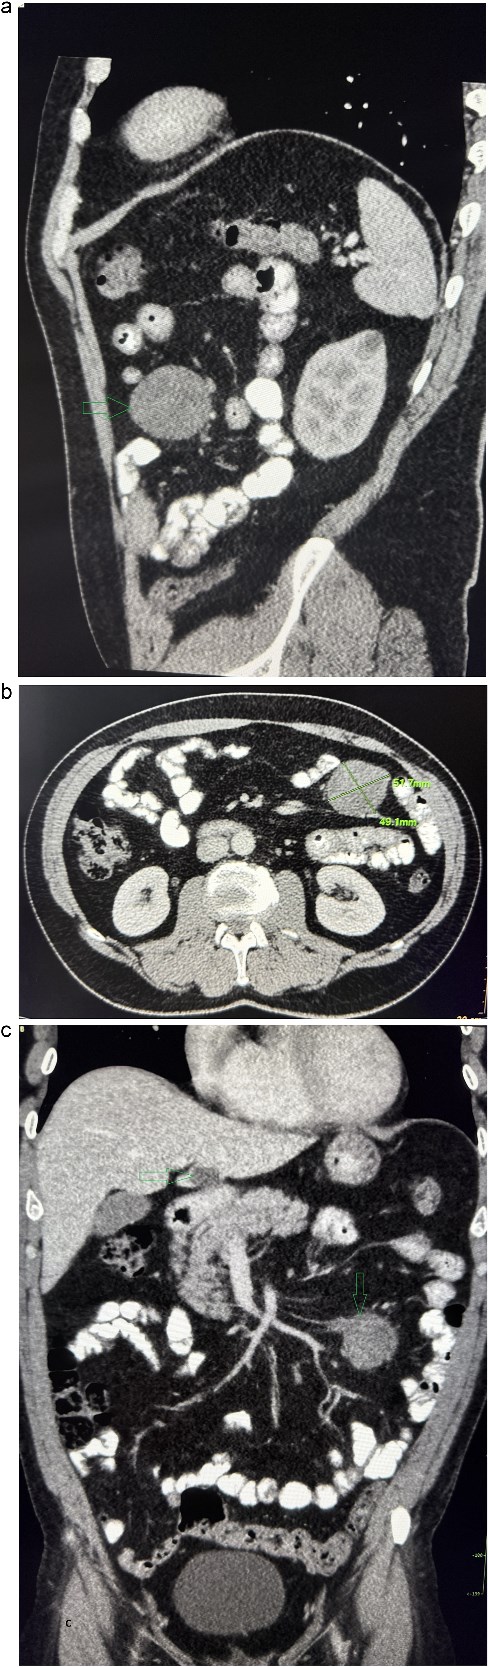

A 53-year-old obese polymorbid patient was initially examined by his general practitioner for 2 months of fatigue. Routine blood tests, physical examination, and X-rays of the lungs were unremarkable. Abdominal ultrasound examination diagnosed resistance in the left mesogastrium and no other pathology was found. The patient was referred to the surgical department for further examination. Abdominal examination was supplemented with computed tomography (CT), which diagnosed a circumscribed hypodense mass of 52 mm at the root of the mesentery in the left mesogastrium and suspected solitary metastatic liver disease (Fig. 1). Massive lymphadenopathy was considered in the differential diagnosis of mesenteric root resistance. Magnetic resonance imaging (MRI) was also indicated to verify the CT findings. MRI examination of the abdomen showed a tumor resistance of 58 × 45 × 45 mm in the root of the mesentery in the left mesogastrium and metastatic liver damage, including lymphadenopathy in the mesentery, was also excluded. The liver mass was diagnosed as a cyst (Fig. 2). According to MRI examination, a possible gastrointestinal stromal tumor, neurogenic tumor, or solitary fibrous tumor was considered as part of the differential diagnosis of mesenteric root resistance. The examination of oncological markers was negative. To investigate the etiology of resistance in the root of the mesentery, a biopsy of resistance was performed under CT control. The biopsy examination showed an ancient schwannoma with positive protein S100 and SOX10 on immunohistochemical examination. Based on the decision of the interdisciplinary indication seminar, the patient was indicated for elective surgery, laparoscopically assisted ileum resection with minilaparotomy in the left mesogastrium. The continuity of the ileum was then restored with a terminoterminal anastomosis sewn by hand seromuscularly in one row with a continuous monofilament suture. The operation went without complications and the patient was discharged on the fourth postoperative day for outpatient care with a fully restored intestinal passage. The tumor-resected ileum was sent for histological examination, which confirmed a schwannoma of the mesentery, which was completely removed (Fig. 3). The surgical wounds were mainly healed. No further dispensary for the patient was indicated.

Abdominal MRI, T1 sequency. The coronal section presents a tumor mass at the root of the mesentery in the left mesogatrium and the liver cyst.